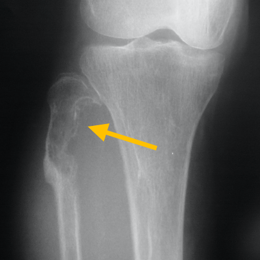

28A) AP XR Of Right Proximal Fibula Hemangiopericytoma (1)

Radiographic imaging is used to help form a diagnosis. These include X-Ray, MRI, CT and Bone Scans